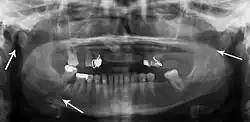

-

Panoramic radiograph of a simple mandible fracture of the right mandibular body, minimally displaced. Note that the teeth to the left of the fracture do not touch -

lateral oblique image demonstrating a fractured mandible.

Towne's view of a bilateral condyle fracture. White arrow is a fracture on the neck of the condyle. Black arrow shows the condyle pulled to the medial. The same injury can be seen on the opposite side -

3D CT reconstruction of mandible fracture, white arrow marks fracture, red arrow marks moderate displacement and open bite -

occlusal radiograph of a mandibular parasymphysis fracture